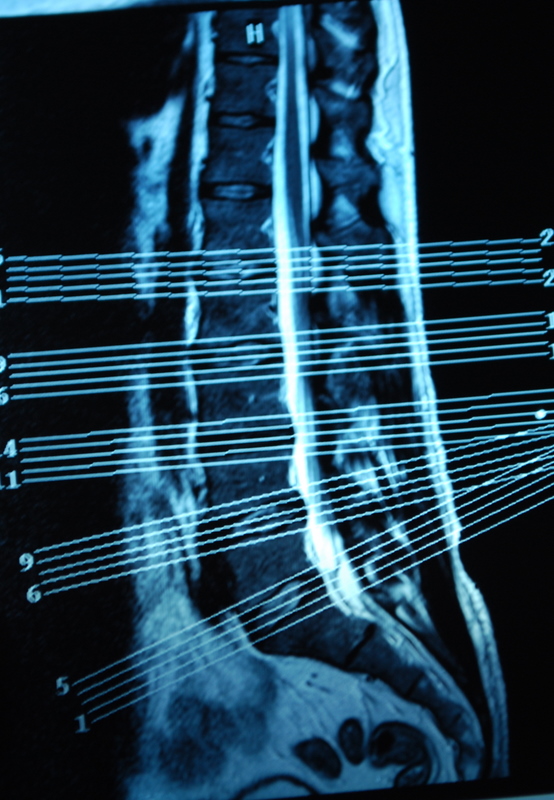

I’ve also come back with copies of my scans. Its very bizarre to sit there and look at slices through your own body. Forget losing weight so you look good in your holiday or wedding photos, try an MRI. There is no turning your best side to the camera or wearing stripes the right way round to hide/accentuate your curves. It shows all your fat, in lovely cross sectional detail. Cath also pointed out that she can see poo in some of the films! Nice…..

Apparently, I’ve also got a dehydrated disc on the next one up (L3/4) which might cause me issues in later life if I’m not careful with impacts, too.